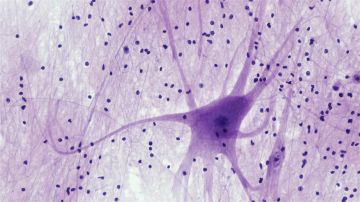

ويعدّ التصلّب الجانبي الضموري مرضا منهكا يدمّر الخلايا العصبية في الدماغ والحبل الشوكي تدريجيا، ما يؤدي في نهاية المطاف إلى فقدان القدرة على الحركة ثم صعوبة التنفّس. وغالبا ما تحدث الوفاة خلال فترة تتراوح بين عامين وخمسة أعوام بعد التشخيص.